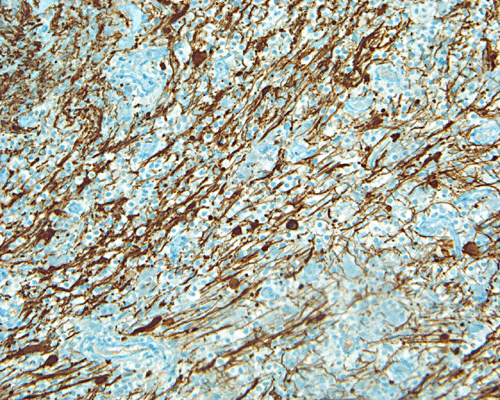

Demyelinating process, immunohistochemistry for neurofilament proteins: This section is taken from a similar area where the image with luxol fast blue-PAS stain is taken. Note the relative preservation of axons. The number of axons far outnumbered the number of fibers with residual myelin. Demonstration of relative preservation of axons is needed when demyelinating disorders are diagnosed.